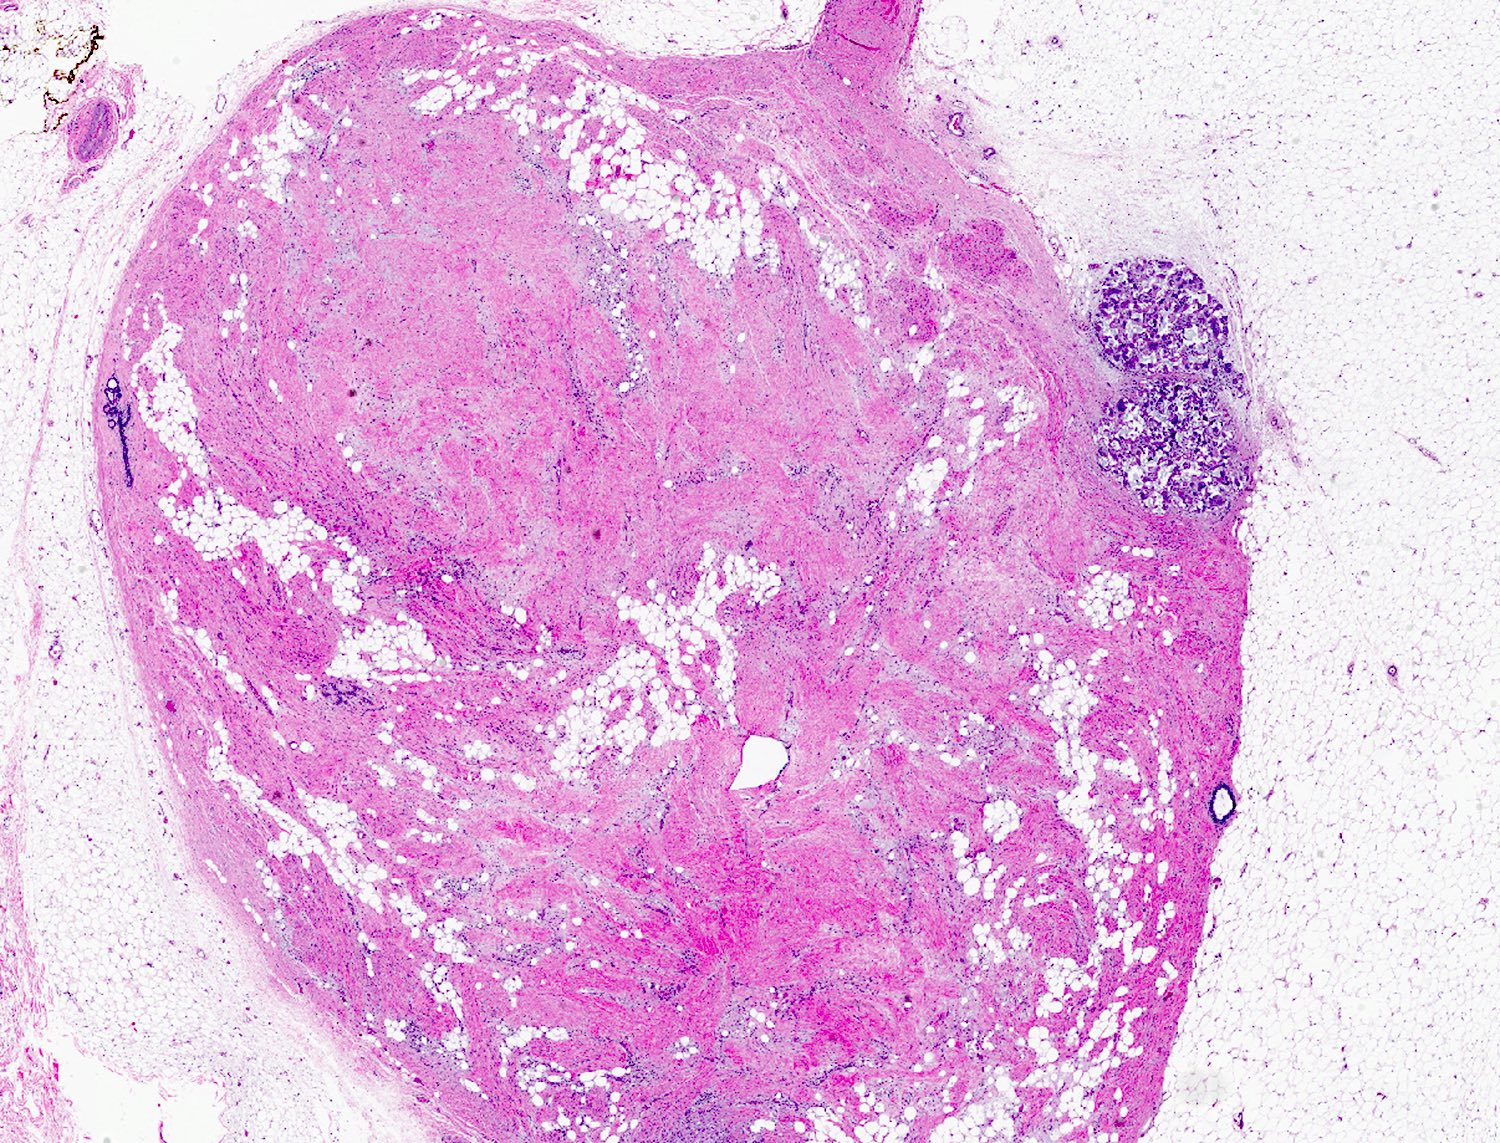

Microscopic (histologic) images

- Well circumscribed, lacks true capsule, rarely infiltrative

- Bland, uniform, short to elongated spindle cells arranged as short haphazard intersecting fascicles admixed with bands of hyalinized, brightly eosinophilic collagen and variable amounts of fat

- No more than mild nuclear atypia

- Mitoses usually absent, atypical mitoses and necrosis absent

- Mast cells common, perivascular lymphocytic infiltrates on occasion

- Focal myxoid stromal changes common